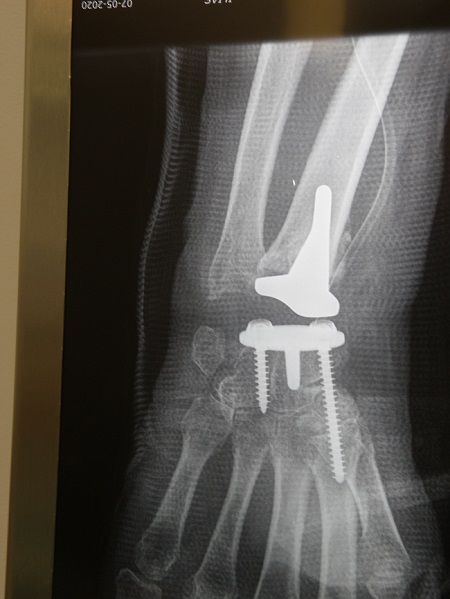

« Η μέθοδος πράγματι αποτρέπει τις αναπηρίες των καρπών μετά από σοβαρούς τραυματισμούς και δίνει εκ νέου κίνηση των δακτύλων και χρήση του καρπού » αναφέρει ο διαπρεπής Χειρουργός Ορθοπεδικός- Μικροχειρουργός Χεριού,Δρ. Ιωάννης Α. Ιγνατιάδης, Διευθυντής Κλινικής Μικροχειρουργικής Άκρων στο Ιατρικό Ψυχικού, που μαζί με την ομάδα του εφαρμόζει τη μέθοδο «πρόθεσης ελεύθερης κίνησης» (freedom),αφού ήταν αυτός που πραγματοποίησε την πρώτη επέμβαση στην Ελλάδα.

Η ομάδα του κ Ιγνατιάδη εφαρμόζει το μοντέλο «ΕΛΕΥΘΕΡΗΣ ΚΙΝΗΣΗΣ» ή “FREEDOM” το οποίο επιτρέπει κίνηση προς όλες τις κατευθύνσεις. Όχι μόνο έκταση-κάμψη, επιτρέπει και ανύψωση βάρους 8-10 κιλών μετά το πρώτο χρόνο από την εφαρμογή του.